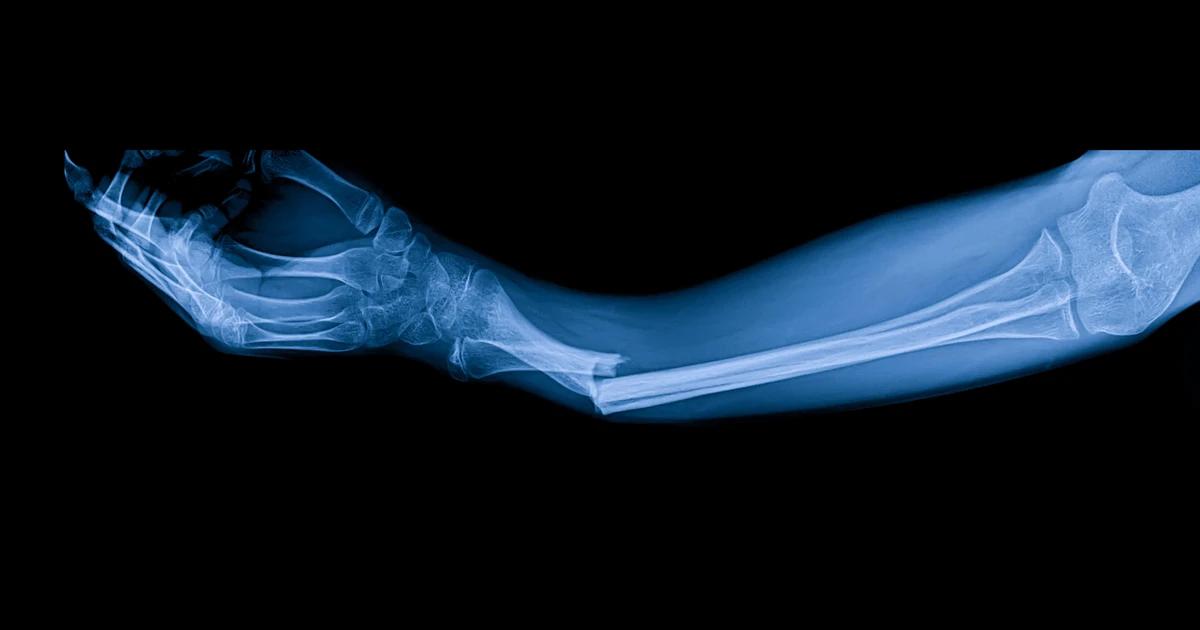

“ერთ-ერთ კლინიკურ შემთხვევაში, პაციენტს, რომელსაც მაჯის მოტეხილობა ჰქონდა, ერთი ინიექცია გაუკეთეს და სულ რაღაც 3 წუთში განიკურნა,“ - იტყობინება ადგილობრივი მედია.

გამოცემის ცნობით, ტრადიციულად, მაჯის აღსადგენად საჭირო იქნებოდა ოპერაცია, ლითონის ფირფიტისა და ხრახნების ჩასმა, რომელთა ამოსაღებად მეორე წელს ხელახალი ოპერაციის გაკეთება მოუწევდა პაციენტს. ანგარიშში ნათქვამია, რომ ძვლის წებოს გამოყენებიდან სამი თვის შემდეგ დადგინდა, რომ პაციენტის მაჯის მოტეხილობა სრულიად შეუხორცდა, ყოველგვარი გართულებების გარეშე.